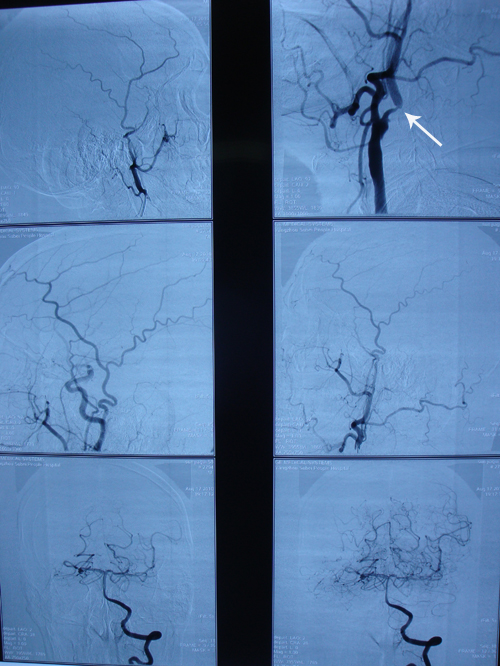

全脑血管造影:右侧大脑中动脉M1段完全闭塞,右侧大脑前以及大脑后动脉侧枝供应该区域。左侧颈内动脉起始段狭窄,最狭窄处达85%,左侧大脑后动脉部分交通支至左侧大脑中动脉供血区域其余血管未见明显异常。